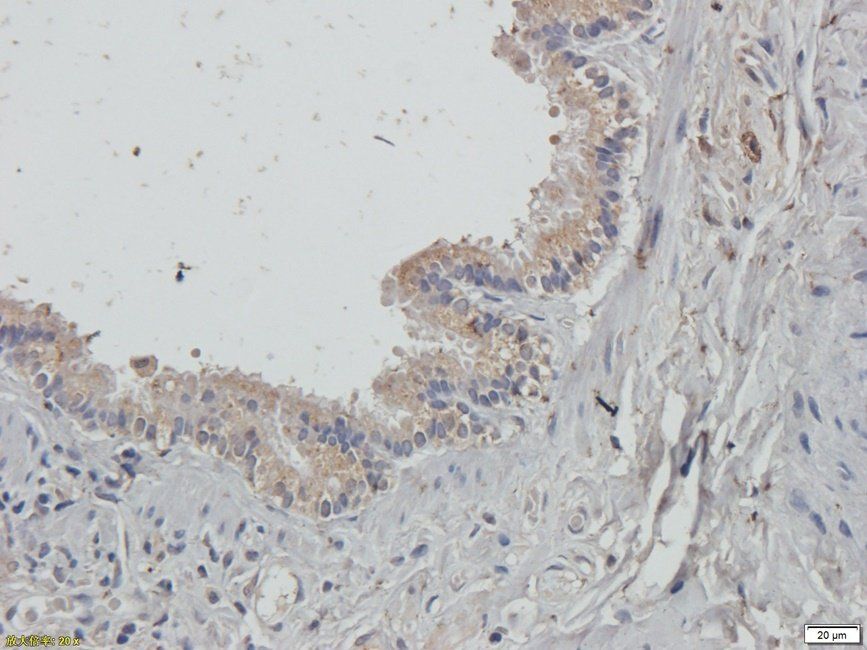

Guanylate Cyclase beta1 subunit antibody

ICC, IF, IHC-P, WB

应用稀释比例:WB: 1-200-2000, IHC-P: 1:100-500, IF/ICC: 1/100-500